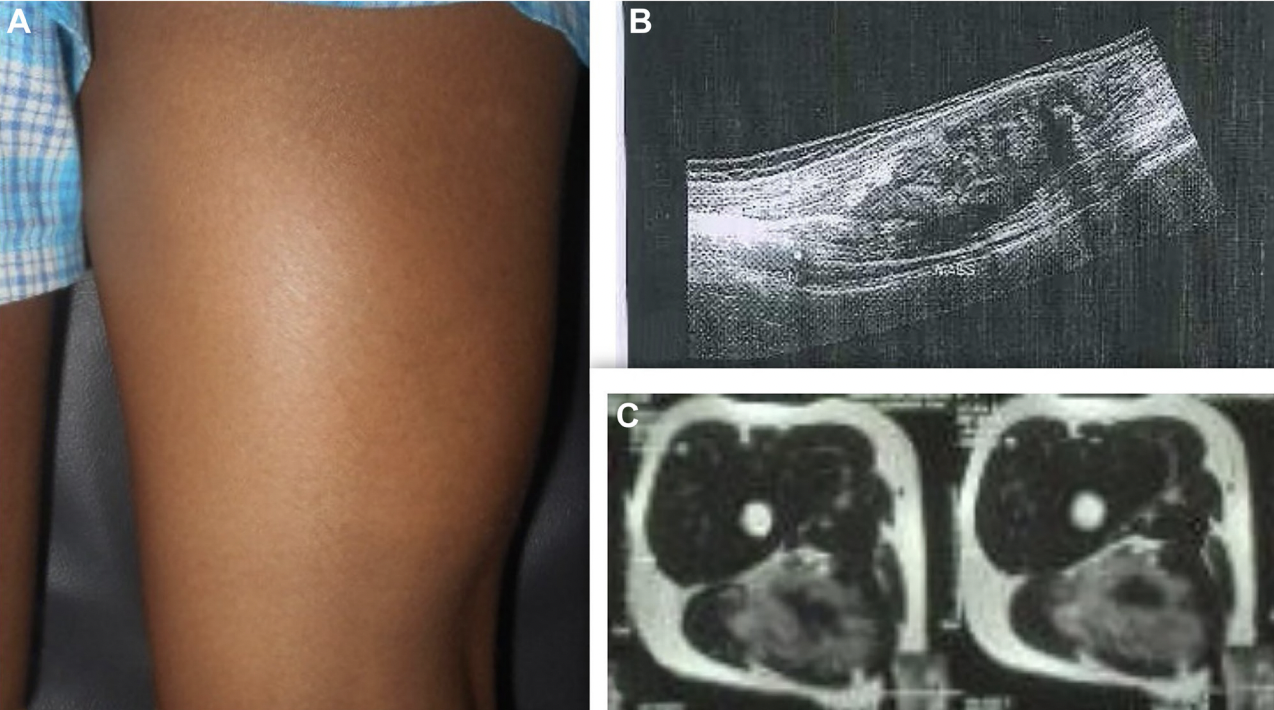

Rare Sciatic Nerve Tumor in Child Successfully Treated with Microsurgery

“This case underscores the importance of meticulous surgical technique, the potential value of IONM, and vigilant postoperative care in achieving optimal outcomes for deep-seated pediatric neurofibromas.” BUFFALO, NY — January 21, 2026 — A new case report was published in…